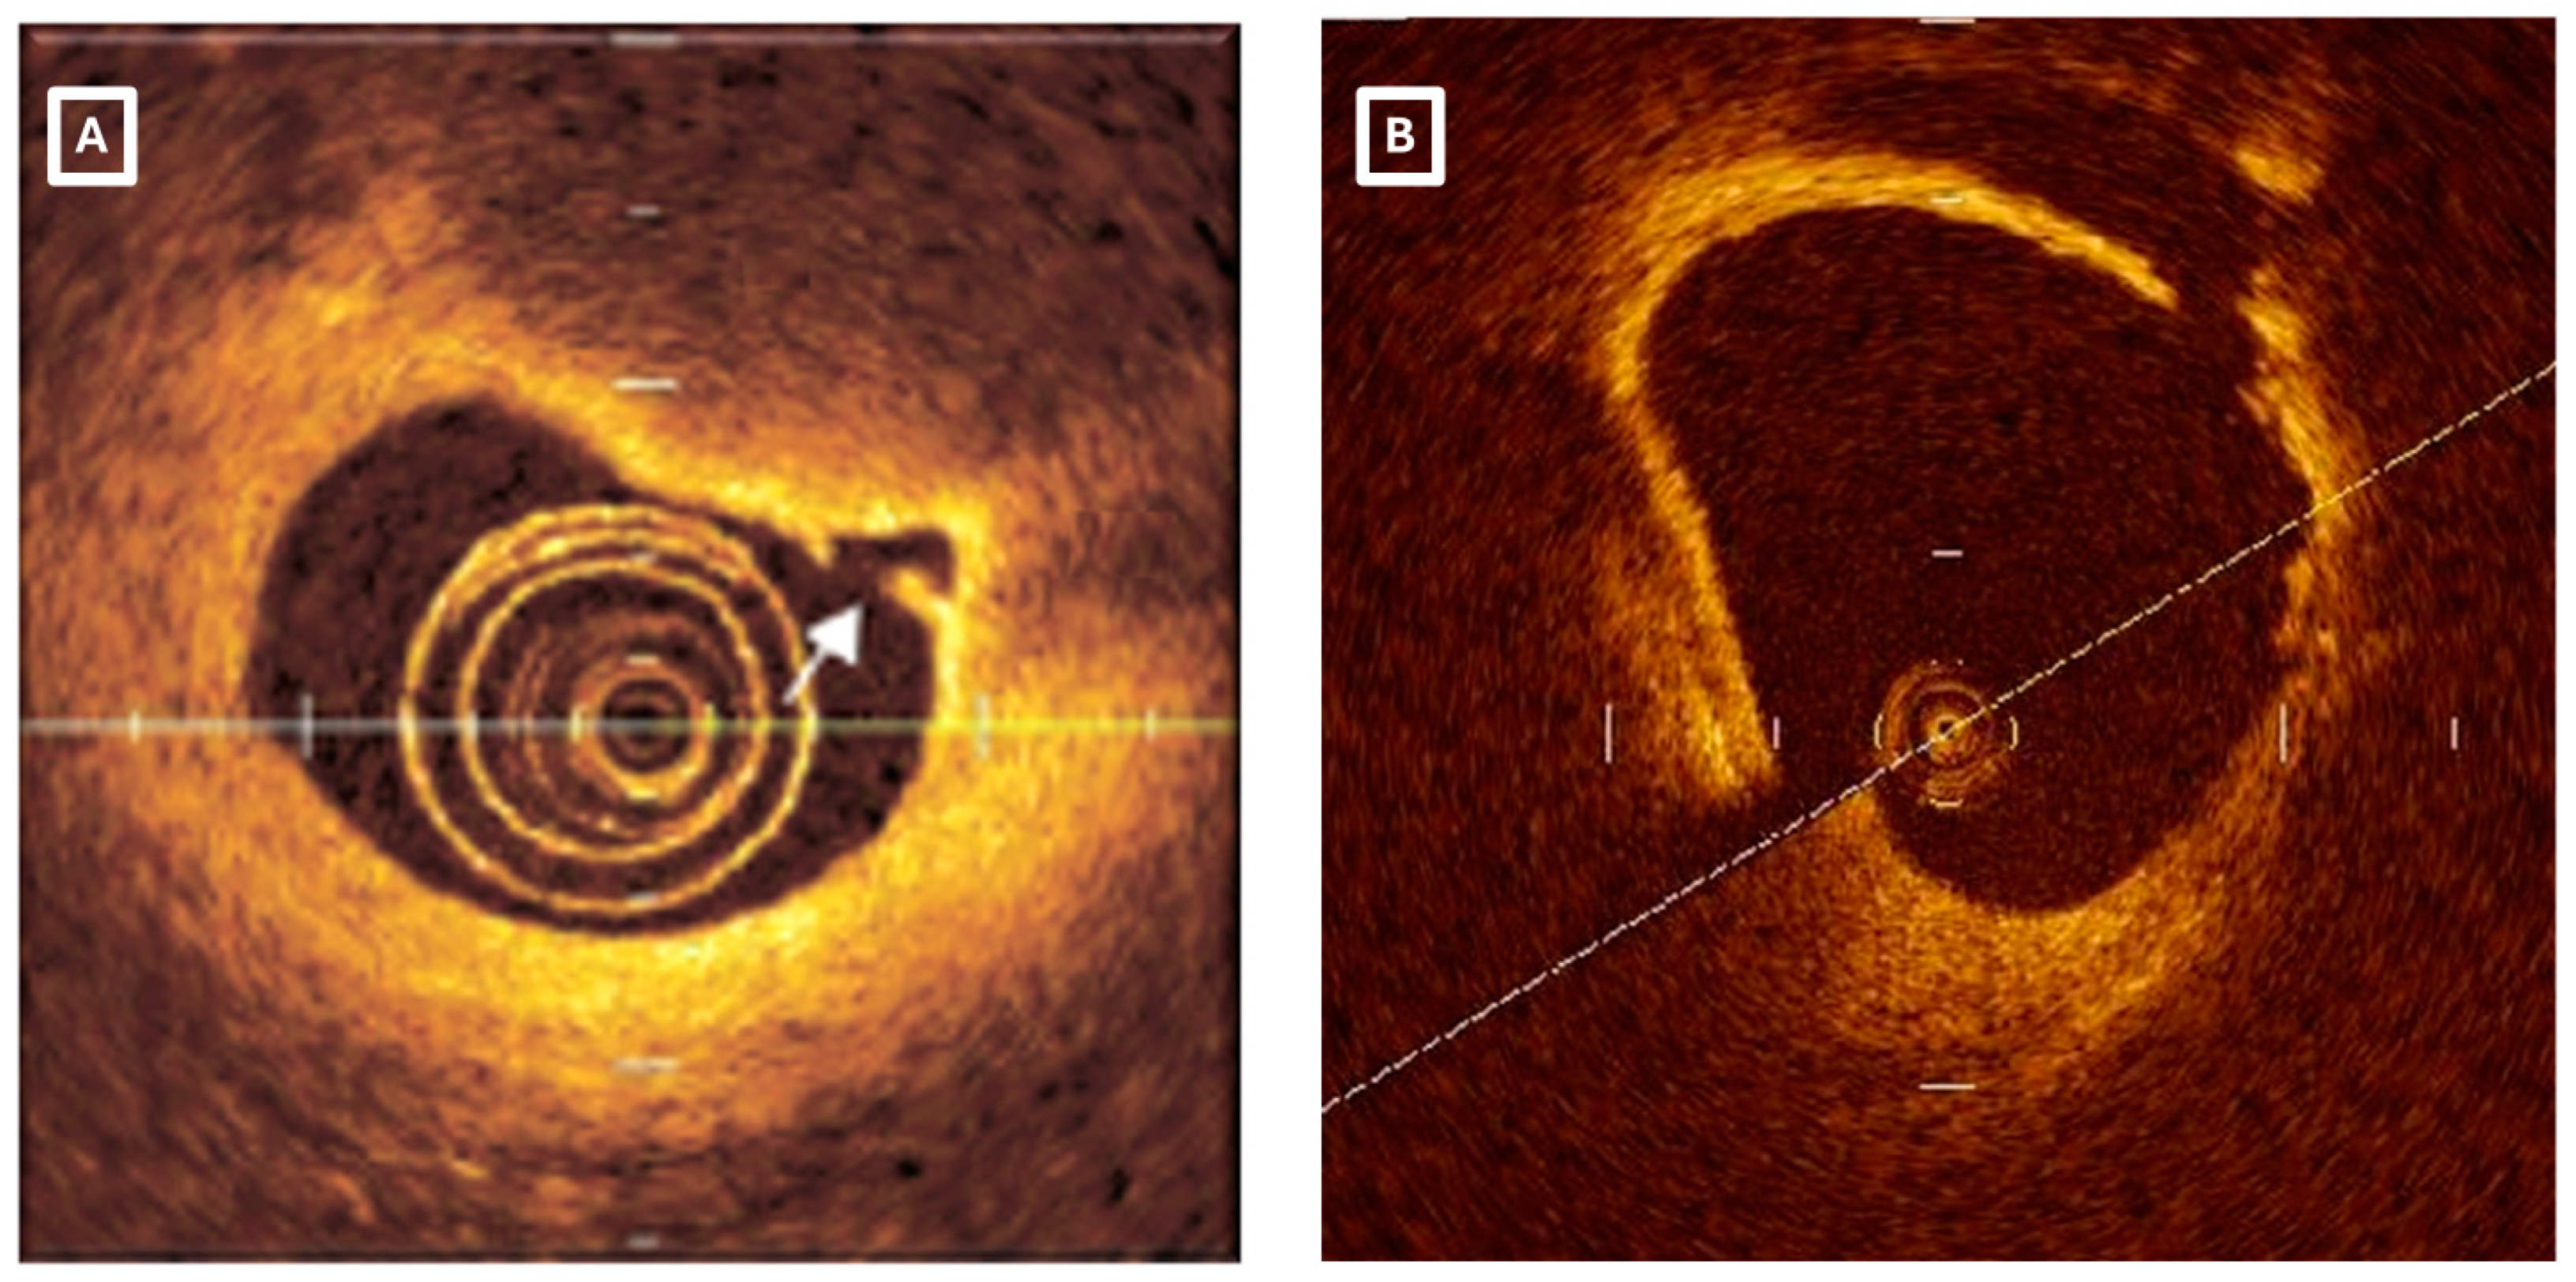

- Tian, J.; Vergallo, R.; Jia, H.; Soeda, T.; Lee, H.; Yu, B.; Jang, I.K. Morphologic characteristics of eroded coronary plaques: A combined angiographic, optical coherence tomography, and intravascular ultrasound study. Int. J. Cardiol. 2014, 176, e137–e139. [Google Scholar] [CrossRef]

- Higuma, T.; Soeda, T.; Abe, N.; Yamada, M.; Yokoyama, H.; Shibutani, S.; Vergallo, R.; Minami, Y.; Ong, D.S.; Lee, H.; et al. A Combined Optical Coherence Tomography and Intravascular Ultrasound Study on Plaque Rupture, Plaque Erosion, and Calcified Nodule in Patients With ST-Segment Elevation Myocardial Infarction: Incidence, Morphologic Characteristics, and Outcomes After Percutaneous Coronary Intervention. JACC Cardiovasc. Interv. 2015, 8, 1166–1176. [Google Scholar] [CrossRef] [PubMed]